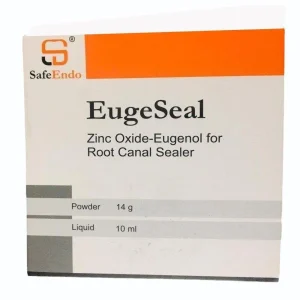

₹1,500 Original price was: ₹1,500.₹1,205Current price is: ₹1,205.

Features- Easily mixed and remains flexible during 2-3 hours Strong bactericidal effect due to thymol iodide Dense canals and microtubules filling (film thickness 3-5 m) Low solubility (0,15%) guarantees longtime lifespan of root filling Radiopaque Significant periapical sensibility reduction (contains Dexamethasone – 0.01%, Hydrocortisone acetate – 1.00%) Description- SafeEndo EugeSeal is a Zinc Oxide Eugenol based…